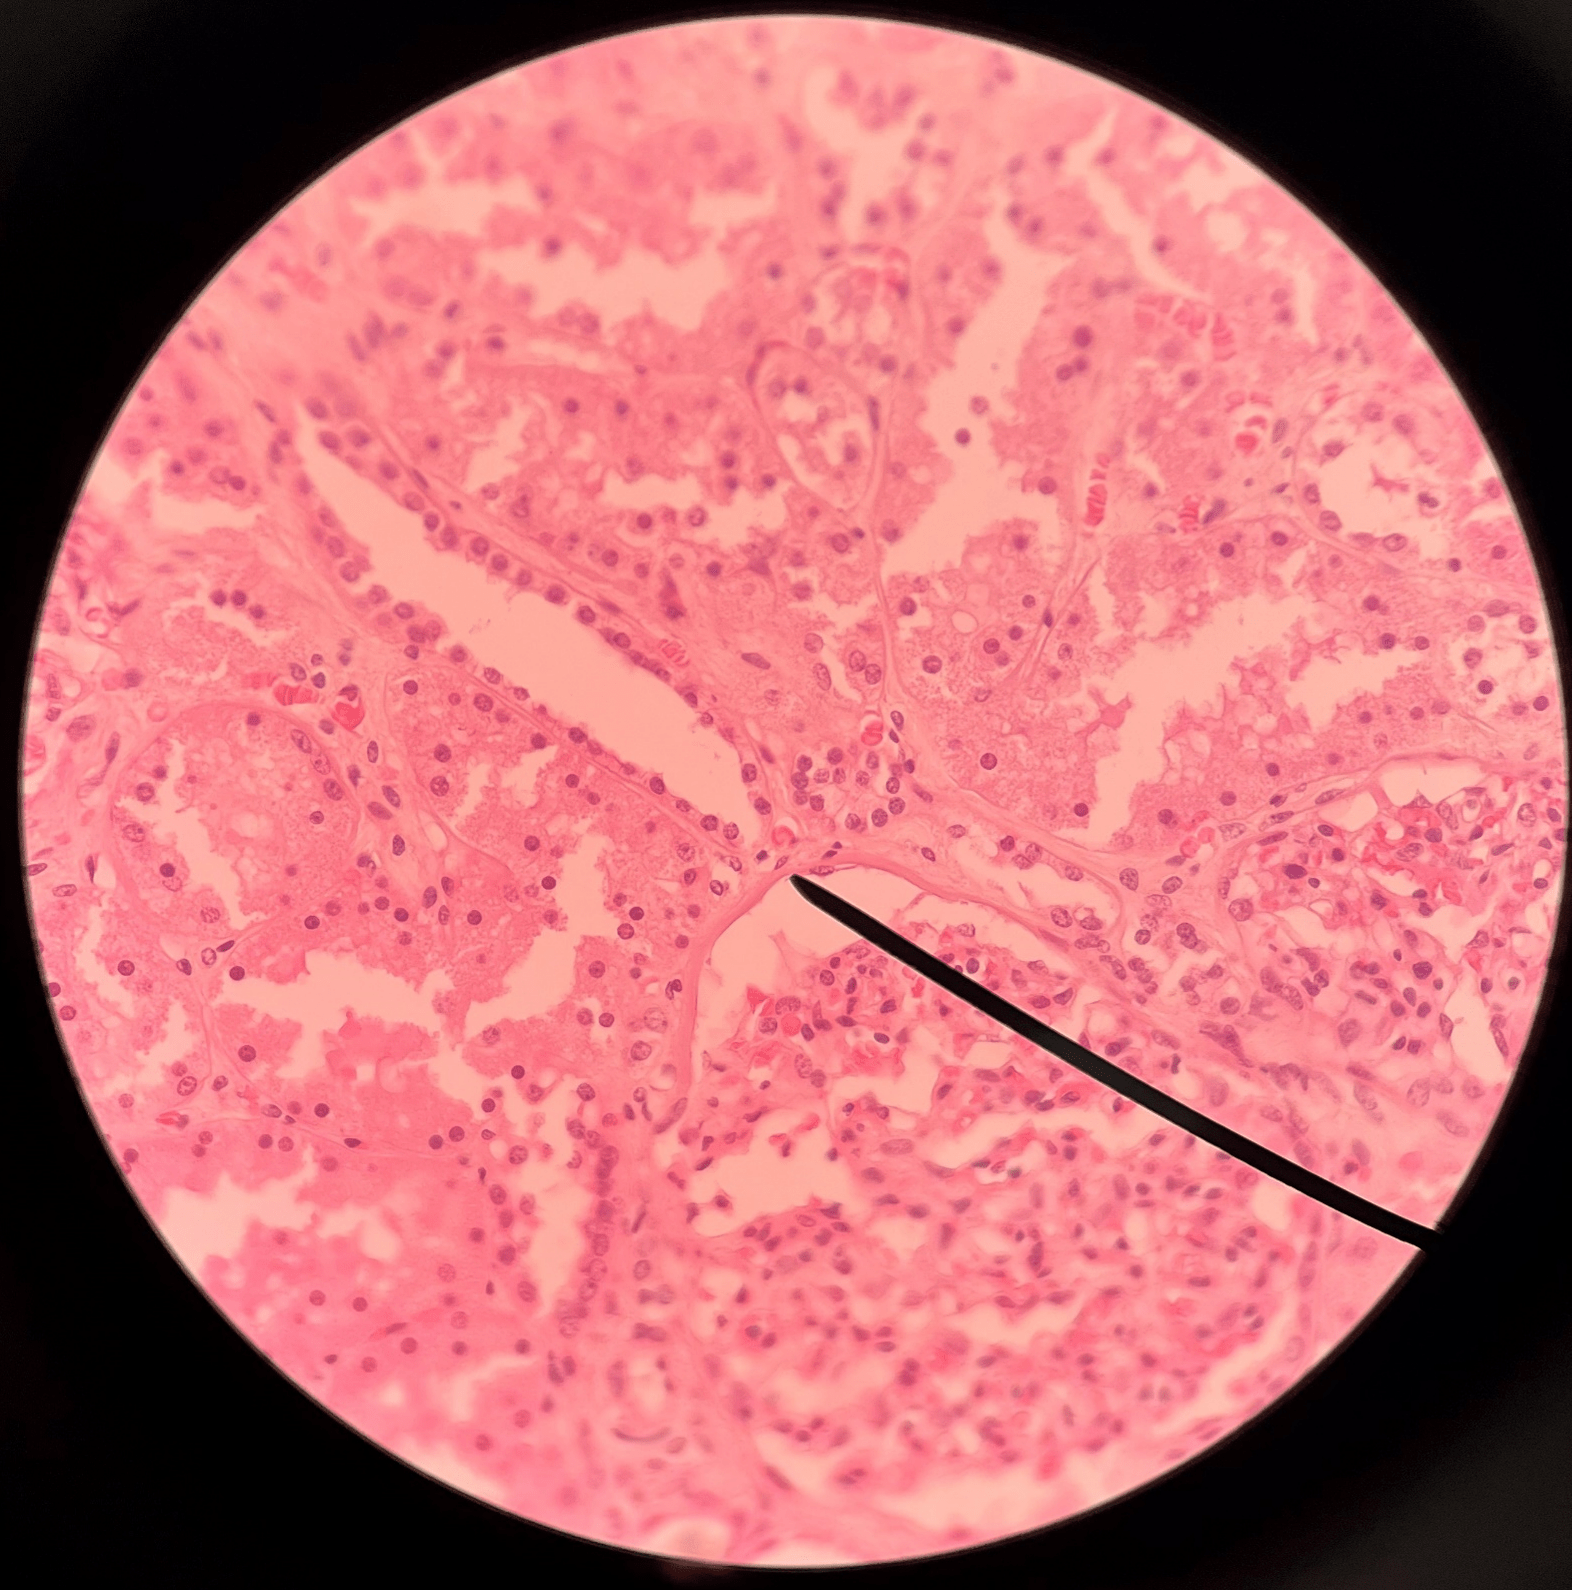

nephron

• The functional subunit of the kidney.

• Site of urine formation and renal function.

• Composed of a renal corpuscle and a renal tubule.

renal corpuscle

• Part of a nephron.

• Filters blood.

• Composed of a glomerulus enclosed within a glomerular capsule.

glomerulus

• Slide histology of the nephron.

• Part of a renal corpuscle.

• The capillary network of a renal corpuscle.

capsular space

• Slide histology of the nephron.

• Part of a renal corpuscle.

• The interior of the glomerular capsule.

glomerular capsule

• Slide histology of the nephron.

• Part of a renal corpuscle.

• A wall enclosing the glomerulus.

• Shown in the image is the parietal layer.

renal tubule

• Slide histology of the nephron.

• Part of a nephron.

• Modifies glomerular filtrate by reabsorption and secretion of water and ions.

• Divided into the proximal convoluted tubule, loop of Henle, and distal convoluted tubule.

proximal convoluted tubule

• The first part of a renal tubule.

• Primary site of water and solute reabsorption.

• Begins immediately after the renal corpuscle.

• Abbreviated PCT.

descending limb

• The proximal second part of a renal tubule.

• Part of the loop of Henle.

• Permeable to water but not solutes.

ascending limb

• The distal second part of a renal tubule.

• Part of the loop of Henle.

• Permeable to solutes but not water.

distal convoluted tubule

• The third part of a renal tubule.

• Primary site of secretion of excess solutes.

• Abbreviated DCT.

collecting duct

• The convergence of several distal convoluted tubules.

• Descends through the renal pyramid.

• Merges with others to form larger papillary ducts that drain into the minor calyces.

• Abbreviated CD.

afferent arteriole

• Branches of an interlobular artery.

• Supplies the glomerulus of a nephron for blood filtration.

efferent arteriole

Vessel carrying blood away from the glomerulus to the peritubular capillaries.

peritubular capillaries

• Branches of an efferent arteriole.

• Supplies the adjacent renal tubules in the renal cortex.

vasa recta

• Branches of an efferent arteriole.

• Supplies the loops of Henle in the renal medulla.